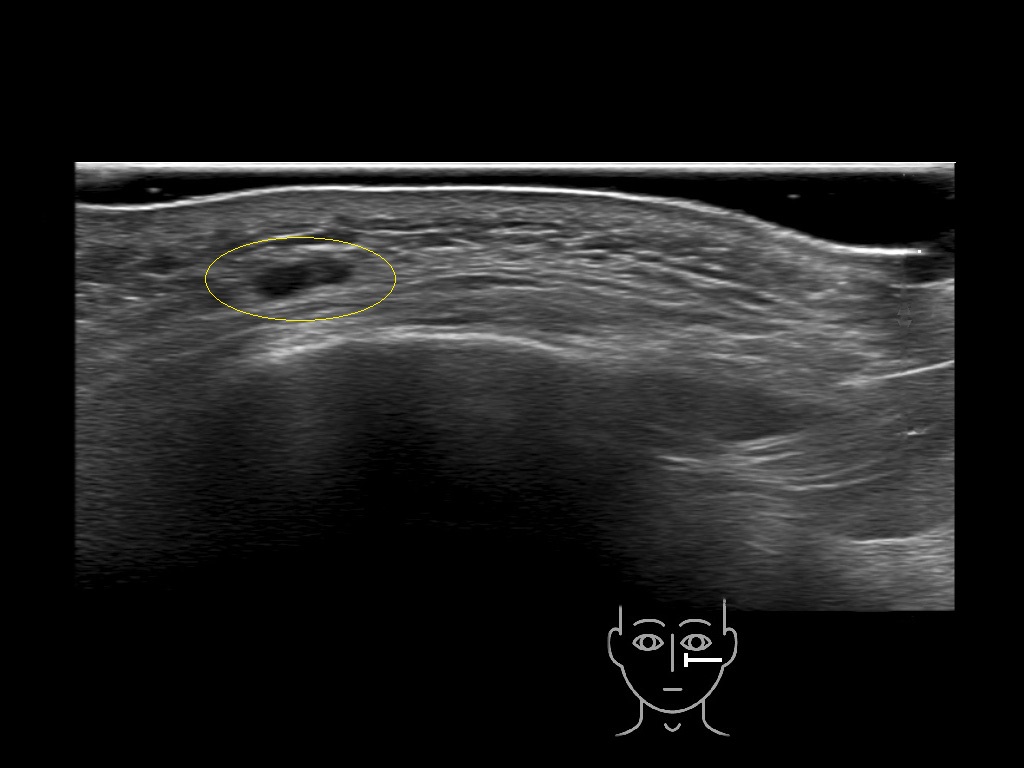

Filler deposits may end up unintentionally in the SMAS or fascial layers of the skin. Very often this will not lead to adverse events, however, adverse events ( nodules, migration / redistribution impaired muscle movement and smiling and malar edema) are are often related to filler ending up in the SMAS or fascia.

Study the first image to recognize the different layers. If you are sure about the layers, swipe to the second image to view the answer (if applicable).